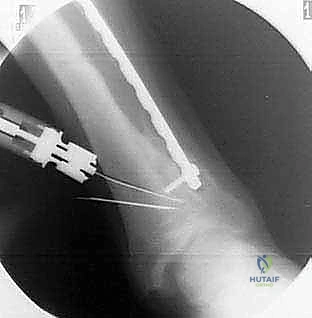

1. التخطيط الجراحي الدقيق (Pre-operative Planning)

يتم إجراء صور أشعة سينية خاصة (طويلة للساق بالكامل أثناء الوقوف) وأشعة مقطعية (CT Scan) ثلاثية الأبعاد. يقوم الدكتور محمد هطيف باستخدام برامج حاسوبية متقدمة لحساب الزاوية الدقيقة للتشوه، وتحديد حجم "الوتد العظمي" (Bone Wedge) الذي يجب إزالته أو إضافته لإصلاح المحور.

4. قطع العظم (The Osteotomy)

هناك تقنيتان رئيسيتان يختار الدكتور هطيف بينهما بناءً على حالة المريض:

* تقنية الوتد المفتوح (Opening Wedge): يتم عمل شق في العظم وفتحه لإضافة طعم عظمي (صناعي أو من حوض المريض) لتعديل الزاوية.

* تقنية الوتد المغلق (Closing Wedge): يتم إزالة مثلث صغير من العظم، ثم إغلاق الفراغ لتعديل المحور.